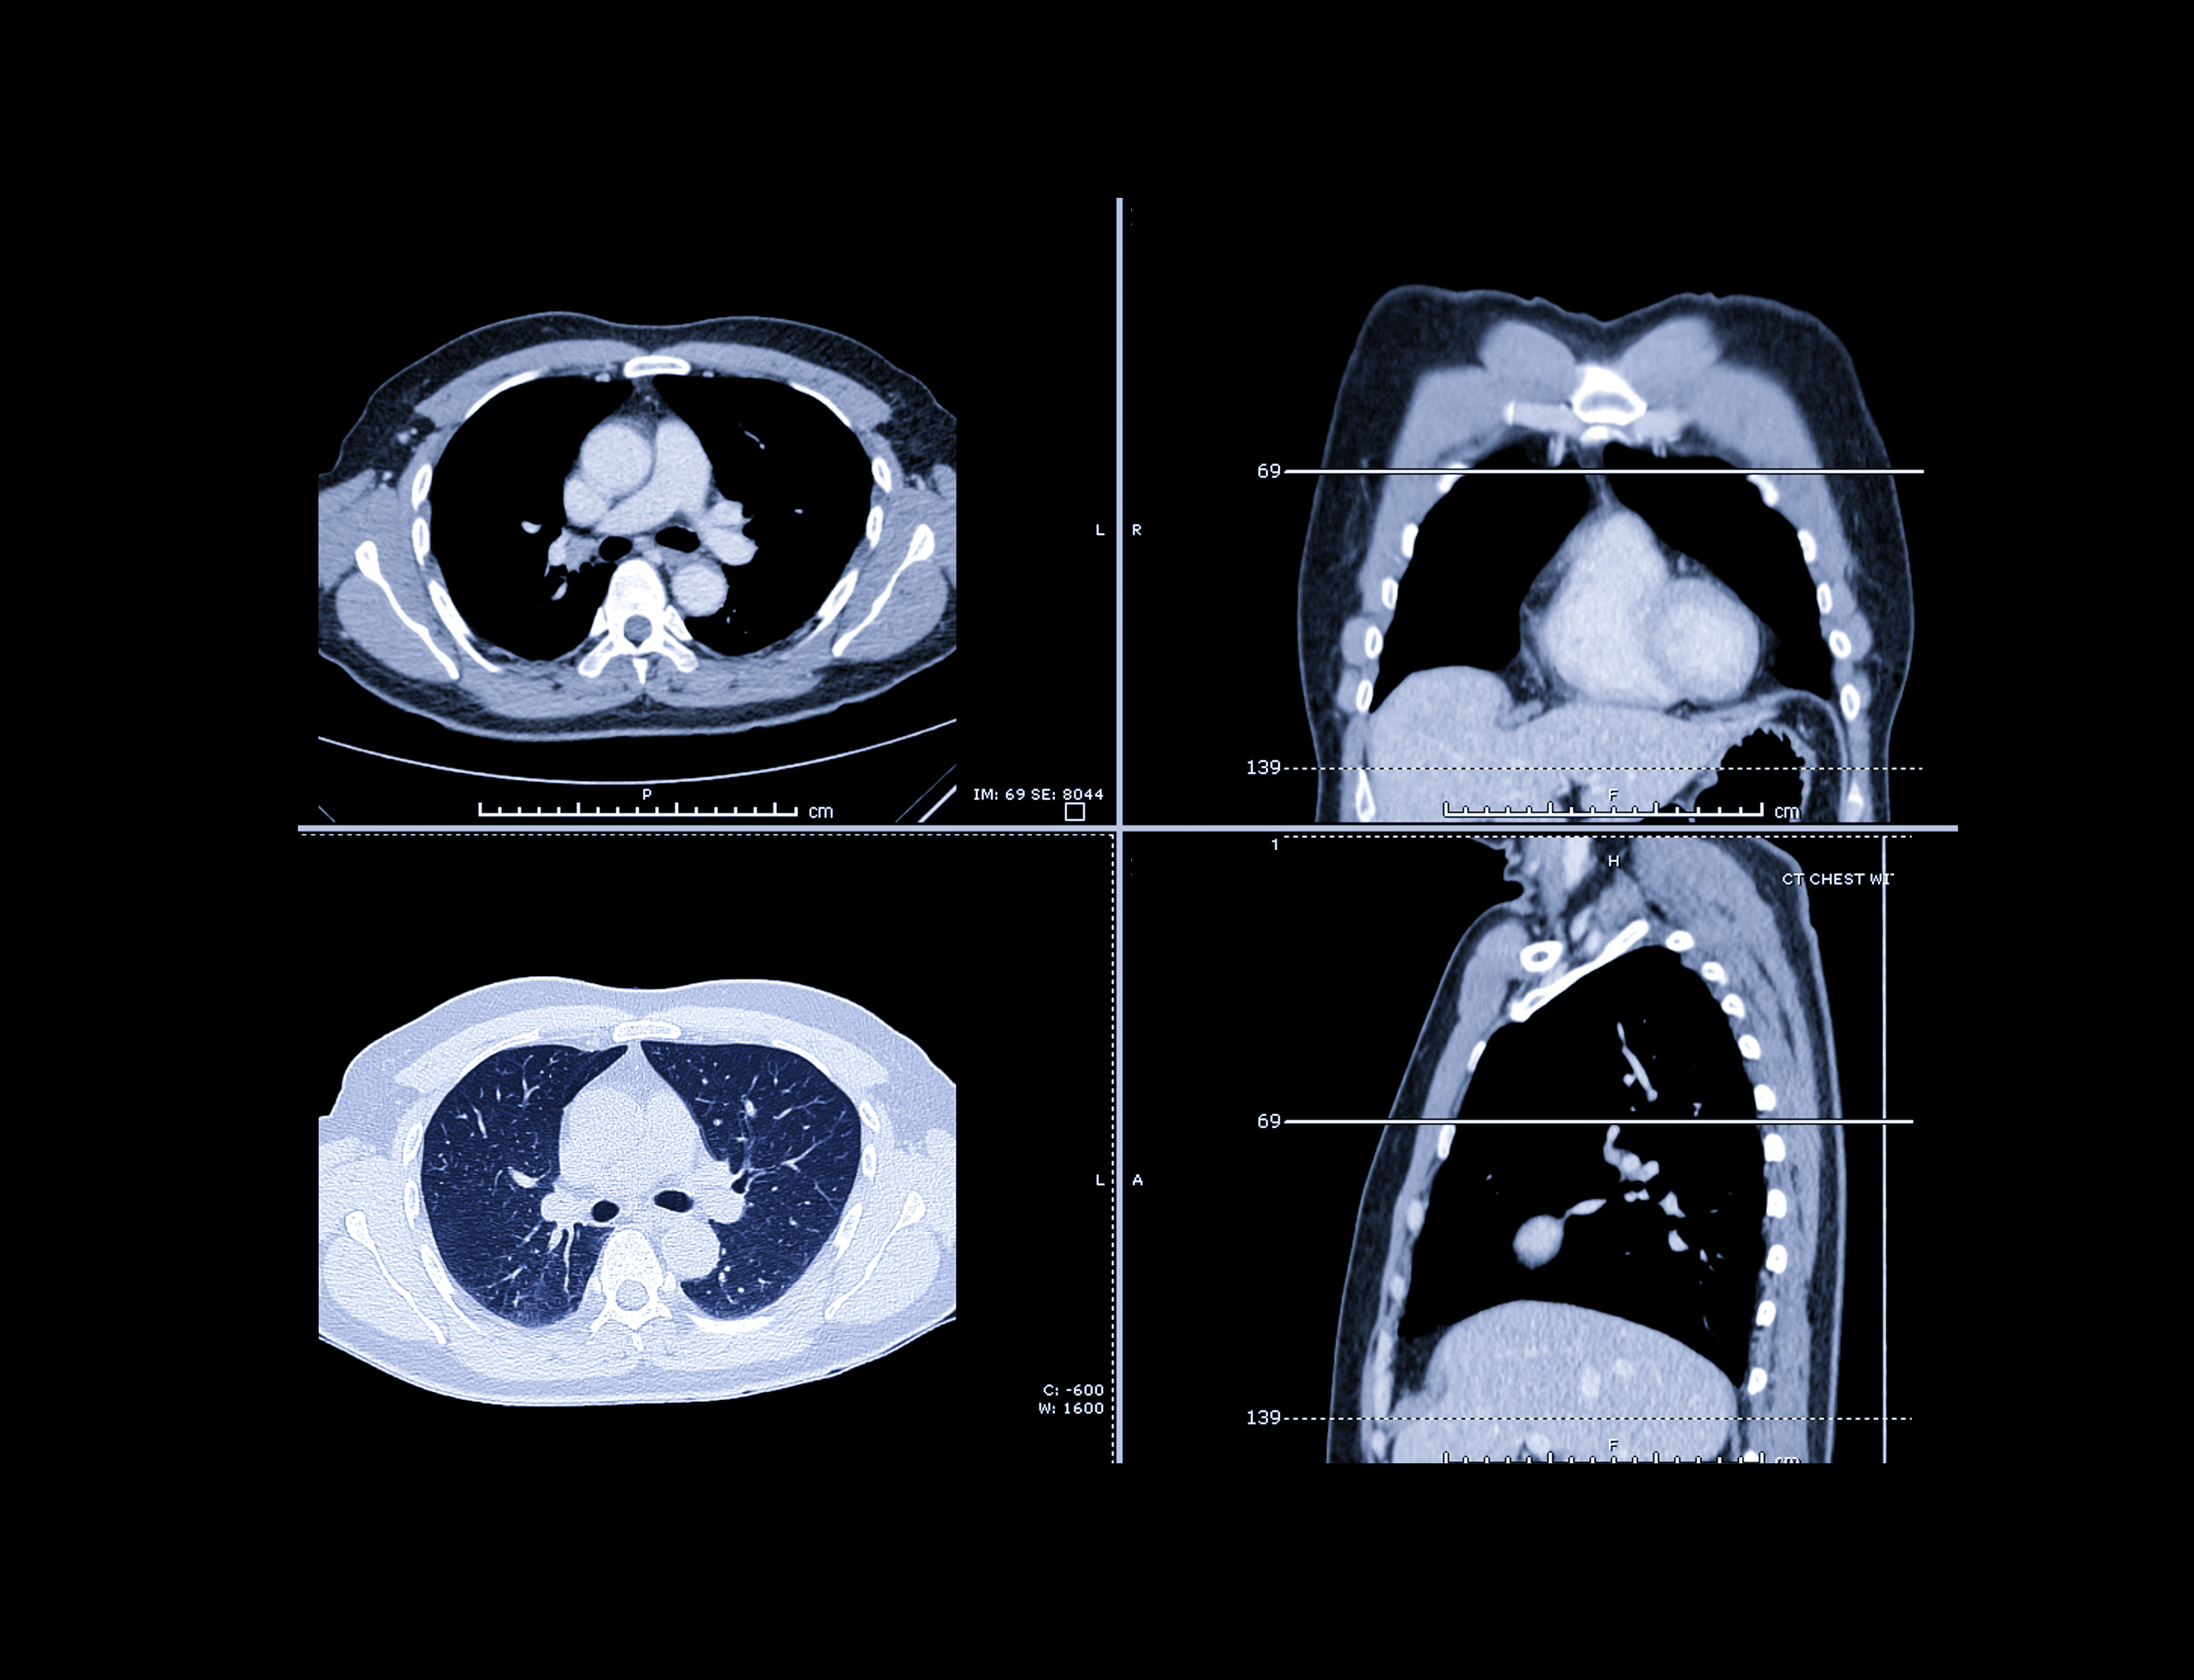

Cespedes-Gomez and colleagues conducted a study that included 1,930 patients between the ages of 50 and 80 who were diagnosed with lung cancer between January 2018 and December 2024. From the medical center's EMR, they culled data such as demographic variables, insurance type, smoking history (pack years, smoking start and stop dates), and evidence of low-dose computed tomography (LDCT) screening within two years prior to diagnosis. They also identified sociodemographic factors associated with missing smoking data and considered predictors of lung cancer screening eligibility.

Of the patients diagnosed with lung cancer, 49% were women, 53% were white, 32% were Asian, 3% were Black, and 12% were of other races and mixed races. Of these, 61% (1,182) had documented smoking history included in their EMR, but only 9.4% of those with complete smoking history who met 2021 USPSTF eligibility criteria for lung cancer screening had undergone it within the preceding two years.